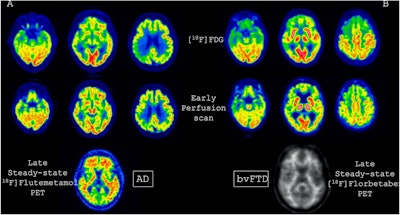

FDG, early perfusion amyloid-PET, and late standard amyloid-PET in a patient with Alzheimer’s disease (AD) ([F-18] Flutemetamol, panel A) and in a patient with behavioral variant of fronto-temporal dementia (bvFTD) ([F-18] Florbetaben, panel B). Regardless of the disease-related pattern (posterior in patient A and anterior in patient B), FDG and early perfusion imaging show largely overlapping distribution with small differences. Higher early-phase amyloid tracer distribution with respect to FDG uptake is expected in the brain stem, cerebellum, anterior cingulate, and thalamus, while lower uptake compared to FDG is present in the prefrontal, orbitofrontal, posterior parietal, and superior temporal regions.Prof. Silvia Morbelli et al and EANM Journal